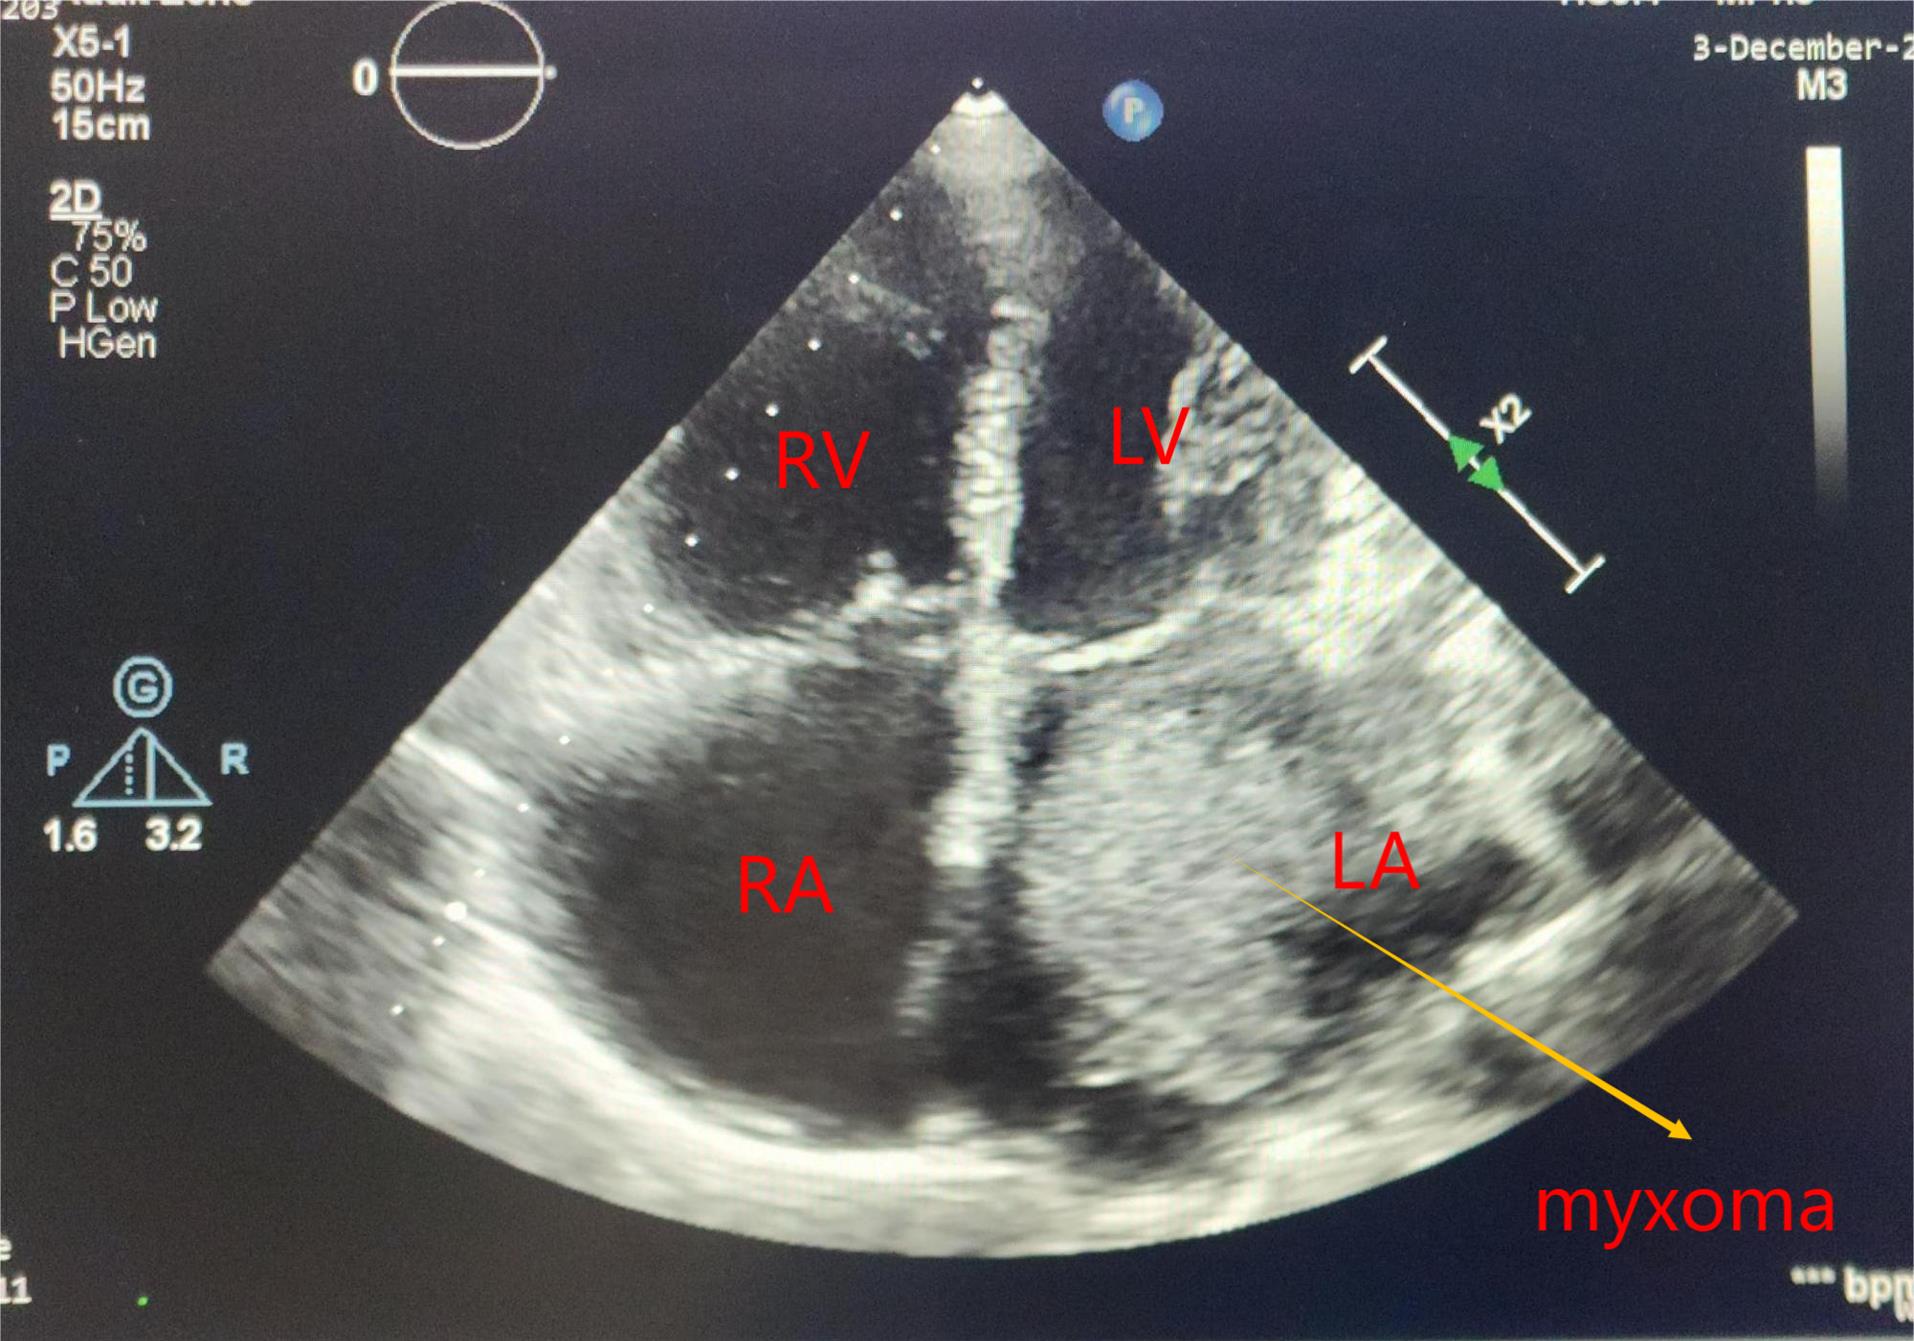

Additional imaging required in the form of cardiac computed tomography (CT) 3 (10%), Contrast enhanced computed tomography (CECT) of thorax 1(3.33%) & cardiac magnetic resonance imaging (MRI) 1 (3.33%), either due to suboptimal quality of TTE or atypical location of the myxoma. MRI brain 1(3.33%) & NCCT Head 1 (3.33%) was performed in patients with history of ischemic stroke. Most common site of myxoma was left atrium 25 (83.33%) as shown in Figure 1, followed by right atrium 4 (13.33%) & right ventricle outflow tract 1(3.33%) with mean size of 5.17 ± 1.46 cm. Most of them were attached to interatrial septum 23 (76.67%). Gross appearance of myxoma shown in Figure 2. Mean preoperative ejection fraction was 55.57 ± 8.59%. Associated valve lesions are shown in Table 2. Concomitant valve surgery performed shown in Table 3. Mitral valve surgery was most commonly performed. Among Mitral valve surgery, 3(10%) were due to Rheumatic valvular disease & 1(3.33%) due to degenerative valvular disease. Remaining Mitral valve surgery 2 (6.67%) due to myxomatous involvement of valve & all 5 (16.67%) Tricuspid valve repairs were done for annular dilatation. Post-operative complications occurred in 6 (20%) patients, most common being superficial surgical site infection 3(10%), followed by atrial fibrillation without conduction disturbance 1(3.33%) & pleural effusion 1(3.33%). Mean duration of intensive care unit (ICU) stay was 4 ± 1.84 days. Mean duration of hospital stay was 16.53 ± 6.57 days. Only one patient (3.33%) died during ICU stay due to low cardiac output syndrome. During follow up, mortality was noted in 2 (6.90%) due to other reasons, one in 1st year & other in 2nd year. Recurrence was observed in 2 (6.67%) during follow up, one after 1- year & one after 3-years of surgery. Long term cumulative and recurrence free survival was analyzed using Kaplan- Meier method as shown in Figure 3 & Figure 4 respectively.

Figure 1.

Echocardiography image of left atrial myxoma